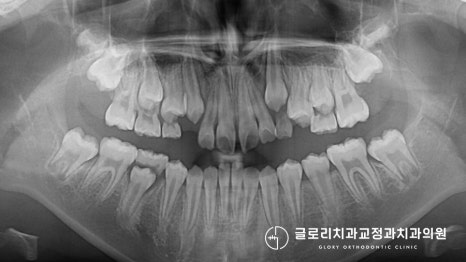

이분의 경우 위, 아래 치아가 거꾸로 물리는

반대교합을 갖고 있었습니다.

그러나 이미 초등학생인 환자의 경우

다소 내원이 늦은 감이 있었습니다.

다행히 아직 영구치가 다 맹출 하진 않았지만

통상적으로 진료를 시작하는 시기에 비해서는

많이 늦은 편에 속하죠.

이런 경우에는 추후 영구치 맹출이 마무리된 이후에

양악 수술을 동반하여 개선을 진행하거나

혹은 치열만 바로잡는 진료를 해야 됩니다.